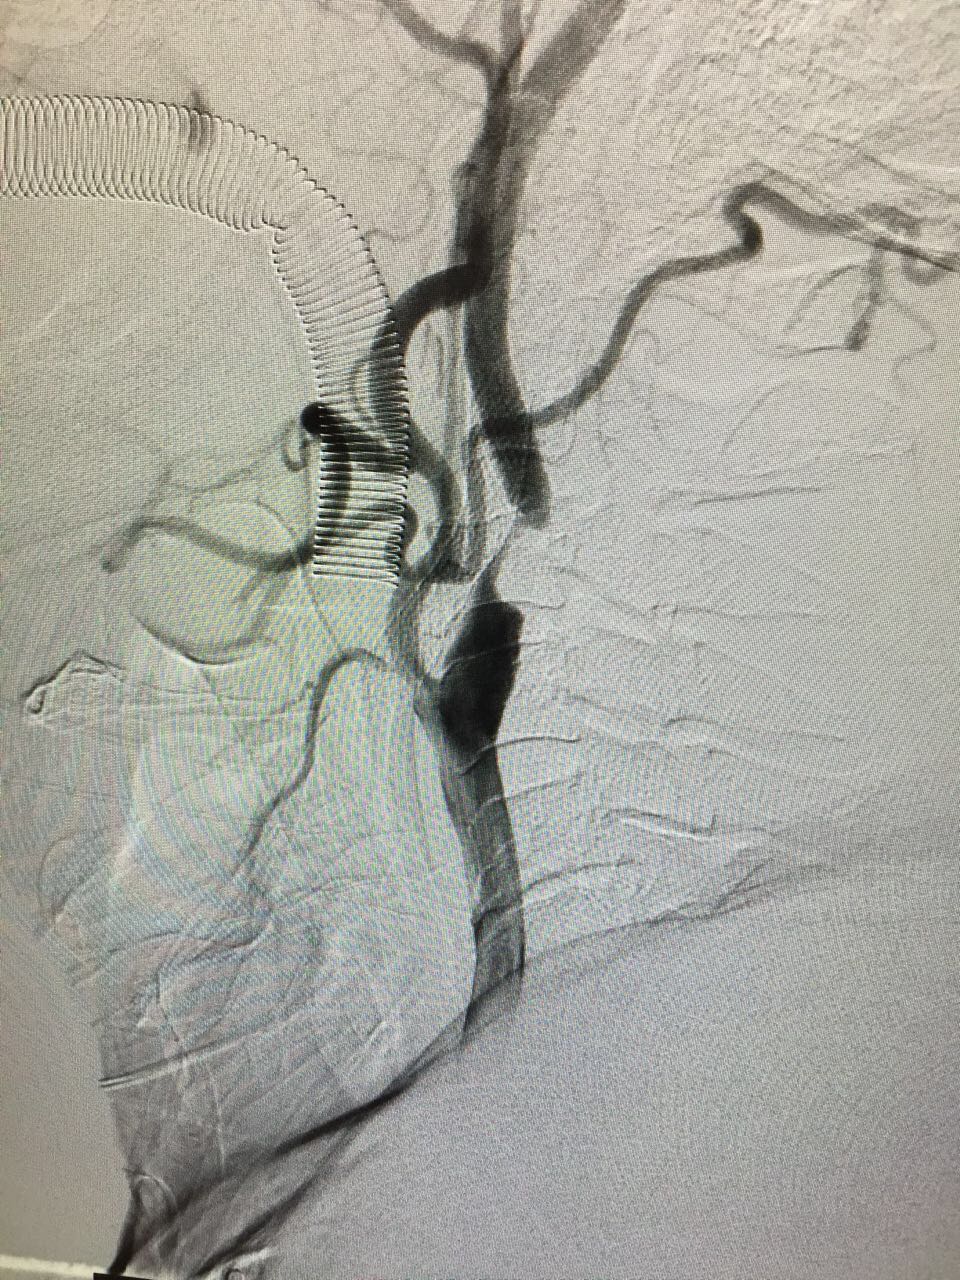

A frame image collection for your cases